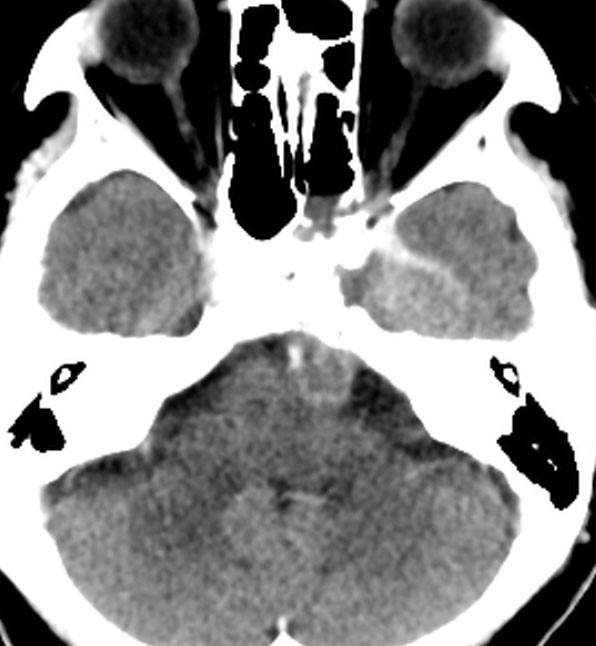

CTでは腫瘍実質部分が増強されます。不規則な骨破壊像・浸食像が特徴的です。

骨軟骨腫が若い時からあって壮年になってから悪性化した軟骨肉腫です。20代のときに右外転神経麻痺が生じて20年以上そのまま経過しました。左のCTでは頭蓋骨の真ん中の斜台というところに異常な骨があって,良性の骨軟骨腫のように見えます。でも右側のMRIでは脳幹部に深く食い込む柔らかい腫瘍の部分が写っていてこれは軟骨肉腫を疑う像です。手術摘出と術後の放射線治療をしました。